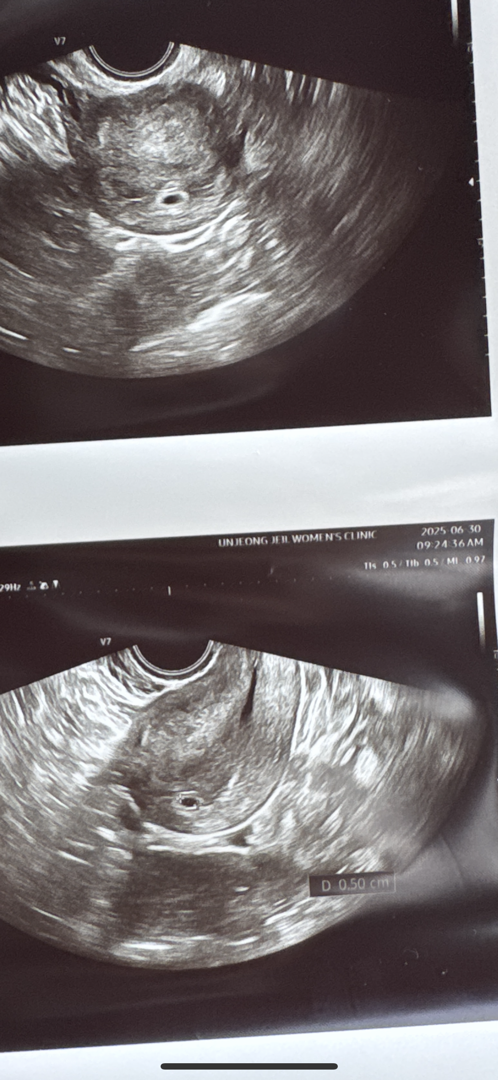

5주0일에 아기집보구왔는데용..

이번주 월요일 첫 진료에 아기집 보구왔었거든요..ㅜ 가운데에 자리도 딱 잘 잡았다구 위치도 좋다고 말씀해주셔서 안심이긴 한데...🤔 이상태라면 다음주 월-화쯤 심장소리 들을수있을거라구 그러시더라구요..? 근데 6주차에 바로 심장소리 들으신분들 계실까요 갔다가 못들을까봐 걱정되고 아직 극초기라 그런가 오만가지 생각에 스트레스받구 힘드네요ㅠㅠ